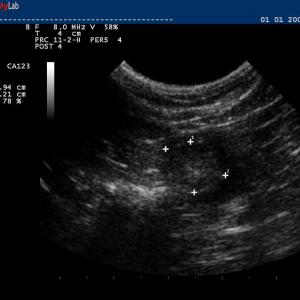

Auch in der Veterinärmedizin wird das schonende Verfahren der Ultraschalldiagnostik zunehmend eingesetzt. Wir verwenden es im Bereich der Abdominal- und Trächtigkeitsdiagnostik .